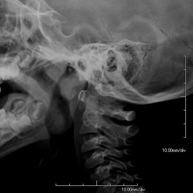

Técnica mediante la cual, utilizando rayos X, se obtienen imágenes de la columna cervical para su estudio. Indicaciones: traumatismo, contractura cervical, dolor articular. - RX Huesos propios nasales

- Cervical spine X-ray

This technique uses X-ray rendered imaging for examining the cervical spine. Indicated for: trauma, cervical pain.